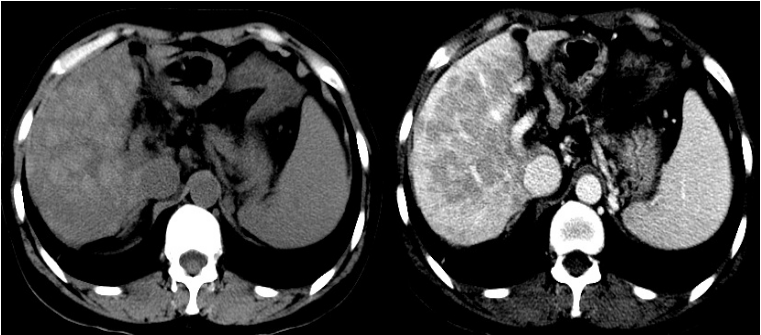

随访本例患者,患者肝移植术后病情稳定,胆红素逐渐下降至正常,凝血功能恢复;不适症状消失;外院肝脏组织标本病理检查结果回报符合药物性或中毒性肝损伤表现,经我院病理会诊意见(图2/3):1.镜下所见:肝细胞桥节坏死及多小叶坏死后塌陷,坏死带内网状纤维塌陷及显著的胆管反应性增生,单个核为主的炎细胞浸润,残余肝细胞再生呈岛状,部分肝细胞淤胆。2.病理诊断:肝组织大块坏死,伴细胆管反应增生及早期再生,符合亚急性肝衰竭表现,免疫组化:CK7(增生的胆管+),CK19(增生的胆管+)。

图2 肝脏大体标本

图3 a:HEx100大片坏死后细胆管反应性增生,

b:CK7x100大片坏死后细胆管反应性增生,

c:HEx40结节状再生,

d:CK7x40结节状再生

在肝移植术后,从患者的肝脏大体标本可以看出,患者肝脏表面已有多发结节形成,肝脏病理提示肝组织大块坏死,伴有细胆管反应增生及早期再生;如患者不进行肝移植治疗,只单纯接受内科治疗,随时有出现新发并发症的可能,肝衰竭进一步恶化,死亡风险增加;即使患者最终缓慢恢复,但有进展为慢性肝衰竭,或形成肝硬化的风险;因此建议该类患者尽早行肝移植治疗,避免继续内科治疗过程中可能出现的病情加重造成死亡,或进展为慢性肝衰竭、肝硬化。